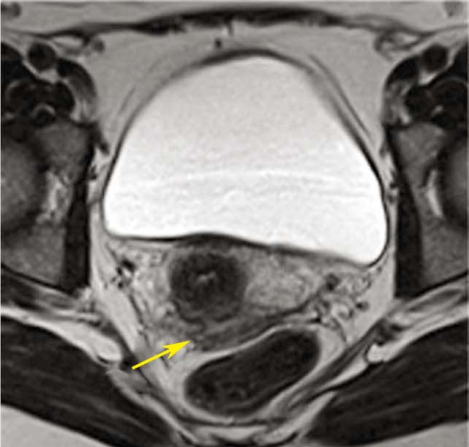

1.影像学检查 超声检查是诊断卵巢异位囊肿和膀胱、直肠内异症的重要方法,可确定异位囊肿位置、大小和形状,其诊断敏感性和特异性均在96%以上。囊肿呈圆形或椭圆形,与周围特别与子宫粘连,囊壁厚而粗糙,囊内有细小的絮状光点。因囊肿回声图像无特异性,不能单纯依靠B型超声图像确诊。盆腔CT及MRI对盆腔内异症有诊断价值,但费用昂贵,不作为初选的诊断方法。

子宫内膜异位症MR